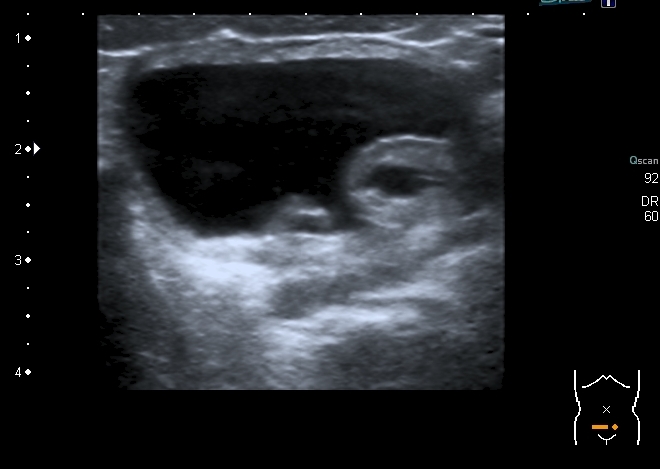

При УЗИ: правая почка - не изменена, в левой - незначительное расширение ЧЛС

В нижней чашечке левой почки - конкремент до 5 мм

Конкремент даёт твитлинг - артефакт

В мочевом пузыре определяется достаточно большое уретероцеле слева, периодически увеличивающееся и пульсационное уретероцеле справа. Левый мочеточник в нижней трети резко расширен.